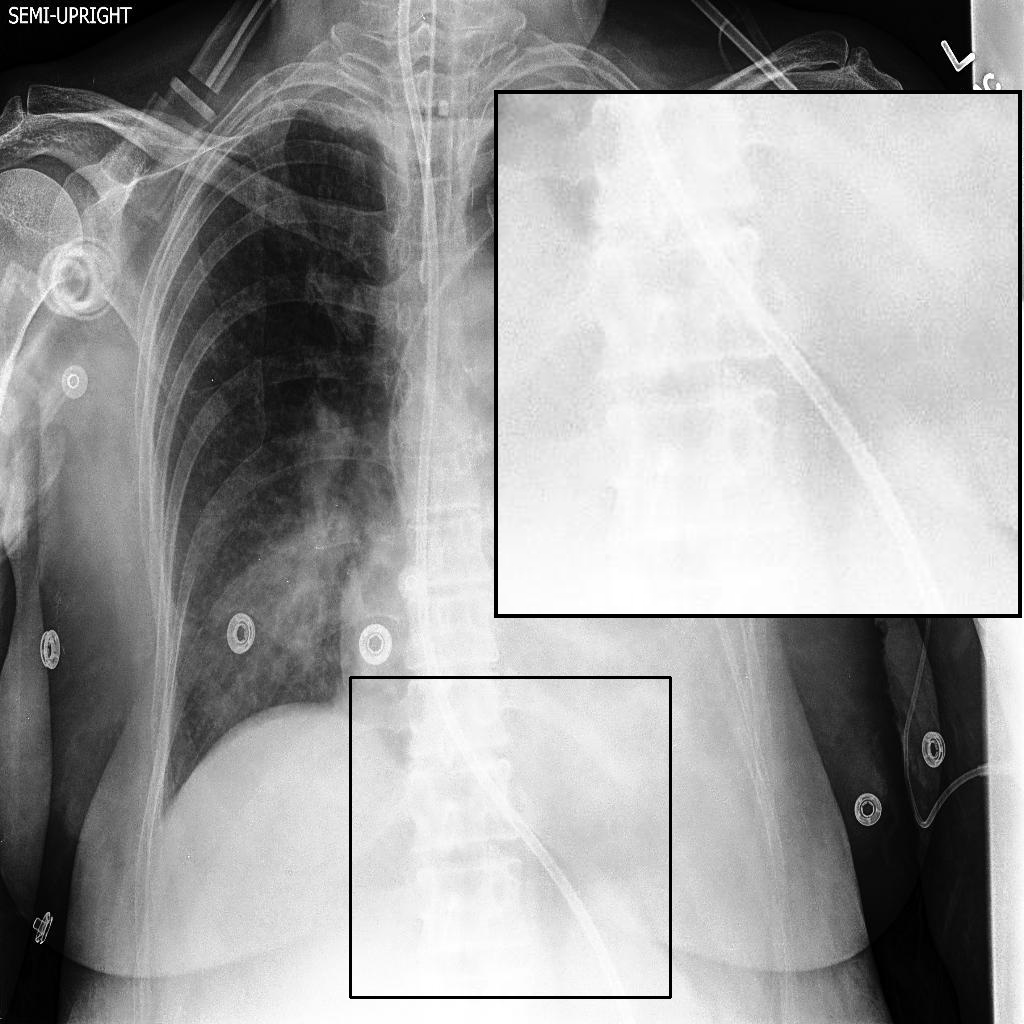

Fig. 3 shows image samples from the above datasets.

Figure 3: Image diversity across four datasets: (a) JSRT, (b) Montgomery County X-ray, (c) NIH ChestX-ray14, and (d) CheXpert